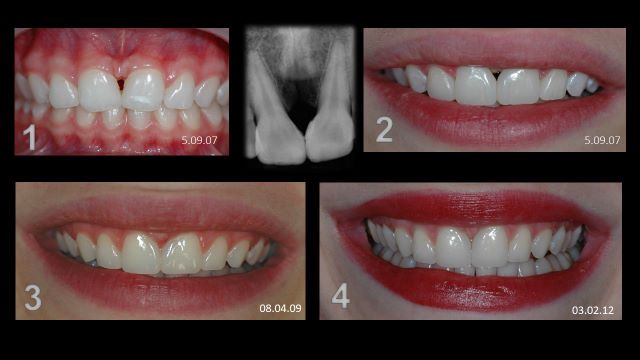

תכנון תלת ממדי של הטיפול האורתודונטי

Suresmile

שורסמייל, השיטה היחידה בה יש לאורתודונט יכולת לשלוט ולתכנן את כל התנועות האורתודונטיות בצורה מדויקת באמצעות כל סמך שהוא בוחר ובכל גישה, (סמכים חיצוניים או סמכים פנימיים או שילוב בין שיטות טיפול).

שורסמייל היא הטכנולוגיה המתקדמת ביותר שישנה כיום בעולם לתכנון מדויק ולהשגת תוצאות אופטמאליות בטיפול האורתודונטי.

שיטה זו פועלת כעשור בארה"ב.